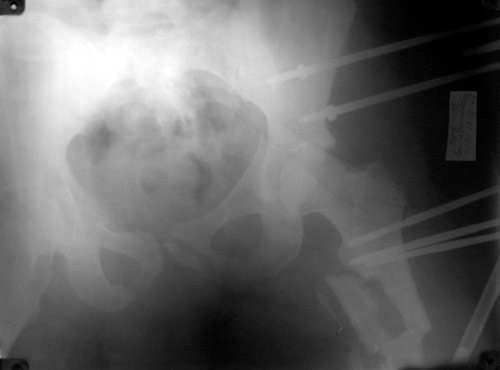

То, что получилось в приложении. Стоит ли дальше тянуть головку винтами или низводить проксимальный отломок по оси?

Уважаемый Борис! Я не имел возможности ознакомиться с рентгенологической картиной сразу после травмы. Имею картинку на данный момент (Ваше приложение). Считаю, что Вы имеете право оставить всё в имеющемся состоянии, но желательна дополнительная дистракция по оси шейки бедренной кости. Далее стабилизировать аппарат. Артроз больному обеспечен, сроки наступления его декомпенсации известны только аллаху.

Можно только порадоваться за пациента и врачей, положение отломков значительно улучшилось. Может быть, удастся добиться "вторичной конгруэнтности" даже при сохраняющемся диастазе на уровне перелома. Из того, что видно - стержней в тазу маловато, лучше бы зацепиться за гребни подвздошных костей (по 3-4 стержня), тогда можно будет пациента и поднять на костыли.

Возможно, и то, и другое. По одной прямой проекции ситуацию не оценить - желательно сделать косые проекции (Judet) левой вертлужной впадины, на которых будет видно, конгруэнтна ли головка со сводом, не надо ли подвинуть ее кпереди или кзади.

По бедру - ось (по одной проекции) и длина восстановлены. Непривычно выглядит стержень с медиальной стороны, мы обычно обходимся только

наружной полуокружностью бедра. Если аппарат здесь предполагается как окончательный фиксатор - похоже, это надолго...

На первый взгляд репозиция вертлужной впадины не плохая, однако следует сделать проекционные снимки по Judet, а вот аппрат конечно подкачал, да и больного жалко. Былобы красиво сейчас после рентген-контроля перкутанно ппровести стягивающие винты через перелом вертлужной впадины из подвздошной в лобковую и из седалищной в подвздошную. А бедро заштифтовать, а потом снять аппарат и отпустить больного, передний отдел возможно фиксировать АВФ.